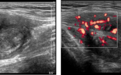

B超检查